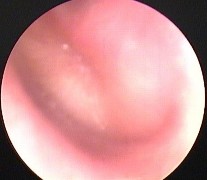

Hình ảnh nội soi tai

Ảnh 6 MN có mức dịch MSBA. 1811255336 |